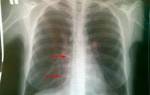

За два дня до госпитализации Иосиф делал рентген легких — они были чистые. В больнице легкие проверили снова, сделали КТ, и оказалось, что за это время успела развиться двусторонняя пневмония. Кроме этого, долго держалась температура, кашель, ломило суставы, но в целом, говорит Иосиф, болезнь протекала комфортно, как ОРВИ.

Решение о выписке пациента с пневмонией принимают, ориентируясь на результаты контрольного исследования. В него обязательно включают рентген.